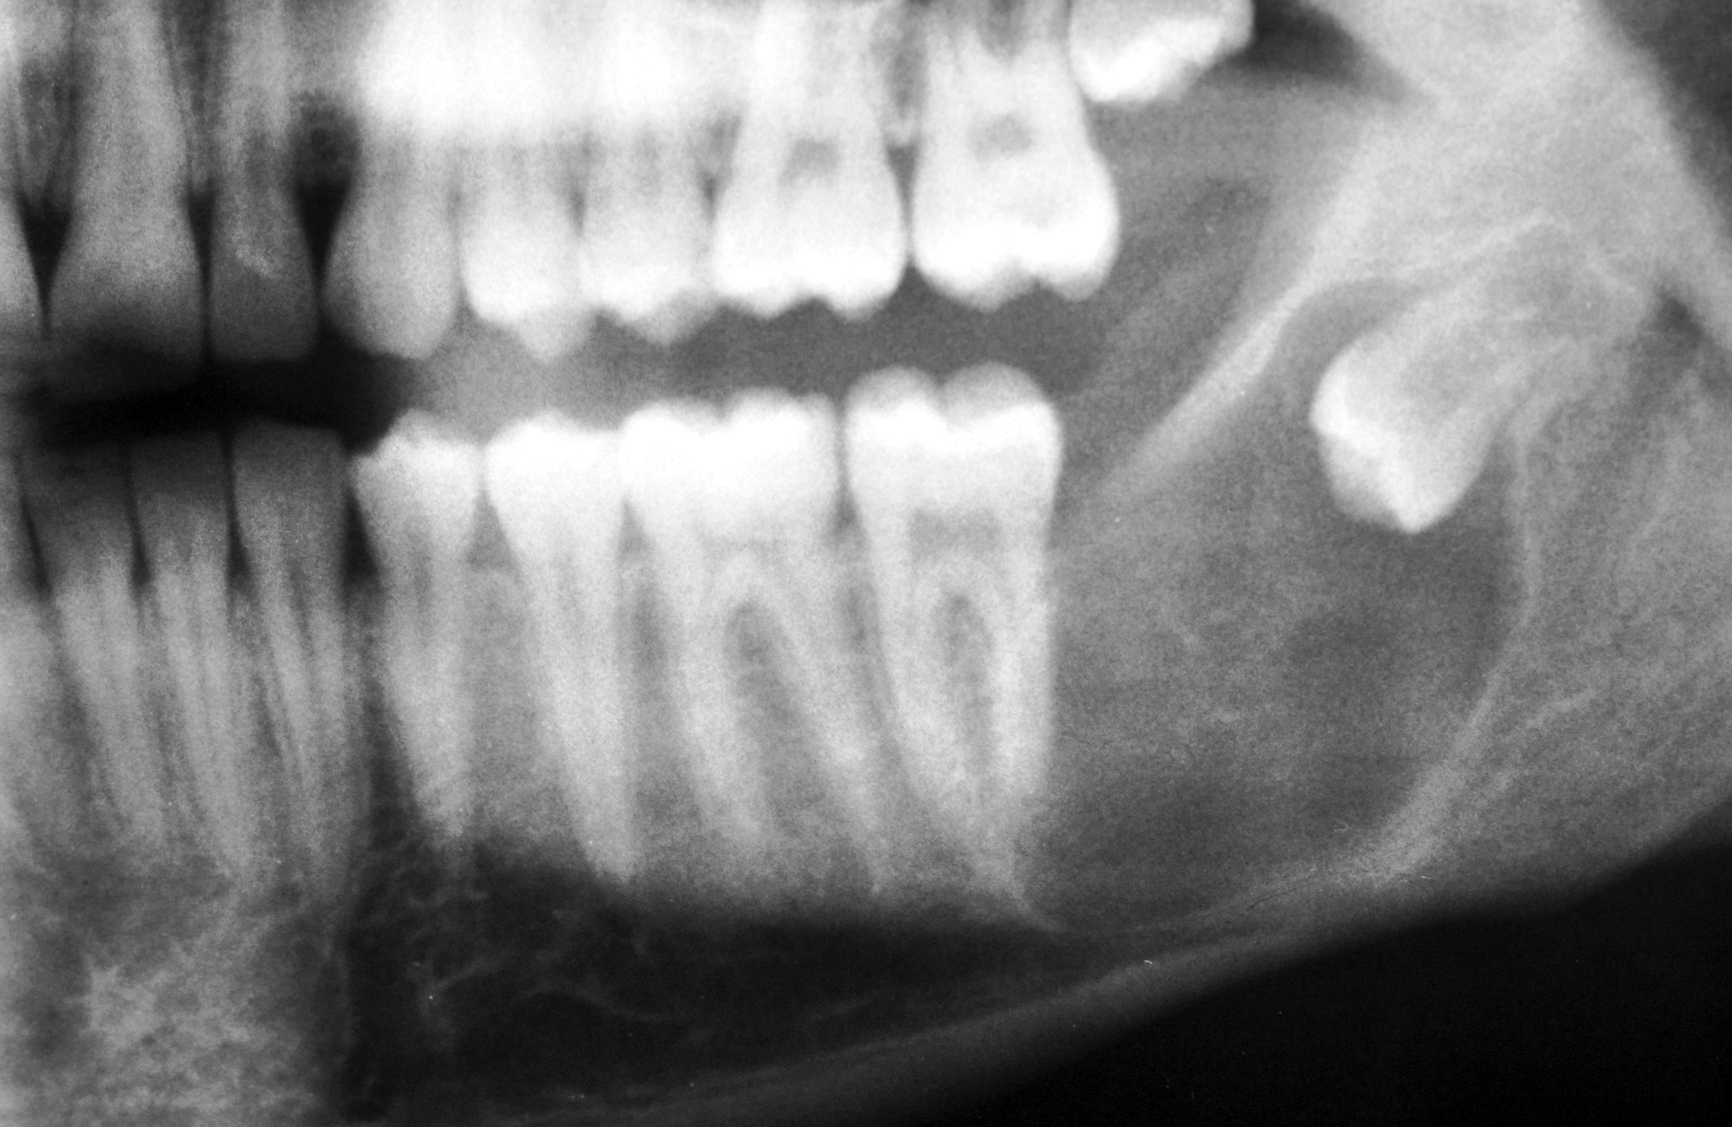

Primordial odontogenic tumor (a) Cropped panoramic radiograph Dental Bone Tumor A person with jaw bone cancer develops a malignant tumor on their mandible, lower jaw bone, or maxilla, which is the hard palate or upper jaw bone. Jaw cancer includes various tumors that form from the tissue involved in tooth formation (odontogenic tissue). An ossifying fibroma is a rare noncancerous (benign) tumor that mostly affects your jawbones. Symptoms are swelling,. Dental Bone Tumor.